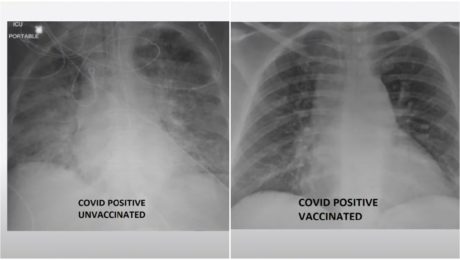

Rozdiel v snímke pľúc zaočkovaného a nezaočkovaného pacienta je diametrálny. Nakazili sa obaja, len jeden je však na tom zle